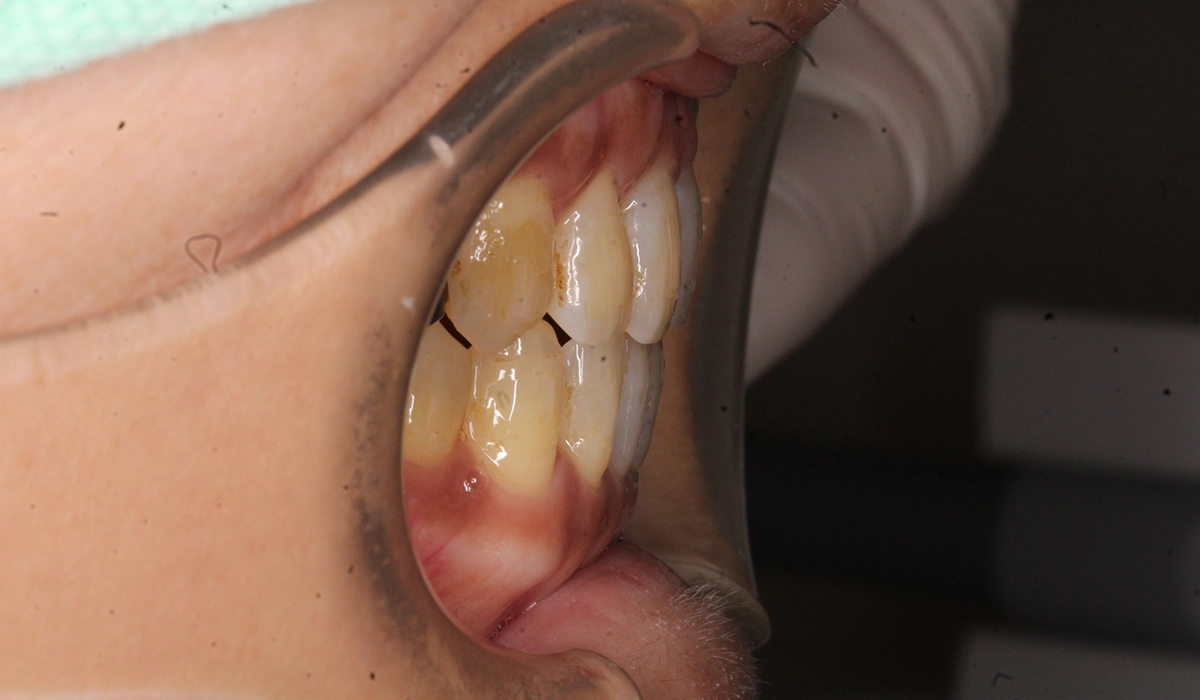

術前:右側